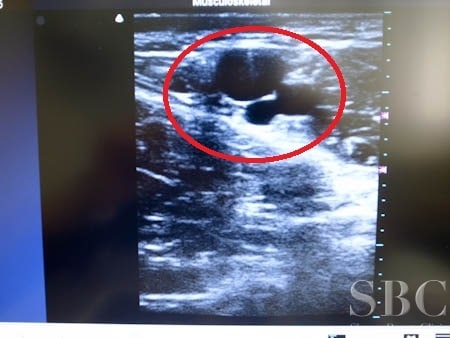

No.100534【わきが・多汗症】湘南美容外科で最も行われているワキのニオイの治療である根こそぎベイザーシェービング法の開発者である根こそぎ竹田先生による根こそぎベイザーシェービング法〜ワキのニオイは解消するもの!根こそぎベイザーシェービング法・右ワキ3Dタッチビュー〜